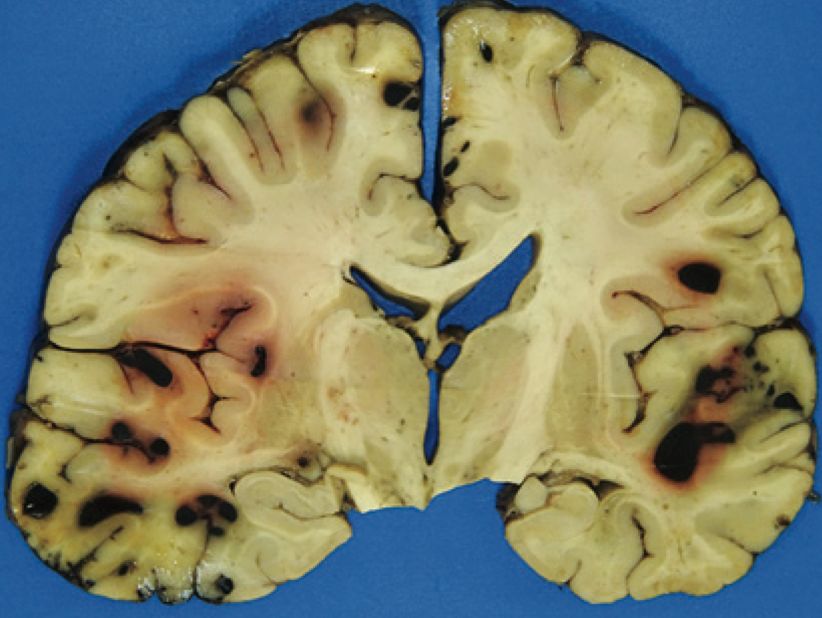

Emorragie multiple osservate nel cervello di un paziente che ha ricevuto T-PA e lecanemab (Fonte: N.J. Reish et al., NEJM)

Una TAC ha mostrato prove di ictus ischemico acuto nella regione temporale-parietale sinistra e l'occlusione di un ramo distale dell'arteria cerebrale centrale sinistra. Non c'erano emorragie. Ha ricevuto un t-PA (tissue plasminogen activator, attivatore del plasminogeno tissutale) anticoagulante per il trattamento dell'ictus ischemico acuto. Durante l'infusione di t-PA, le sue condizioni sono peggiorate. Una risonanza magnetica ha mostrato diverse aree di nuovo sanguinamento su entrambi i lati del cervello.

In seguito è morta e, all'autopsia, aveva ampie emorragie con gonfiore in tutto il cervello. Aveva anche una deposizione di amiloide-beta nelle pareti dei capillari del cervello, nonché le tipiche placche amiloidi e i grovigli neurofibrillari del MA. Questa amiloide all'interno delle pareti dei vasi sanguigni cerebrali è chiamata 'angiopatia amiloide cerebrale' (CAA), ed è una delle cause principali delle emorragie cerebrali negli anziani.